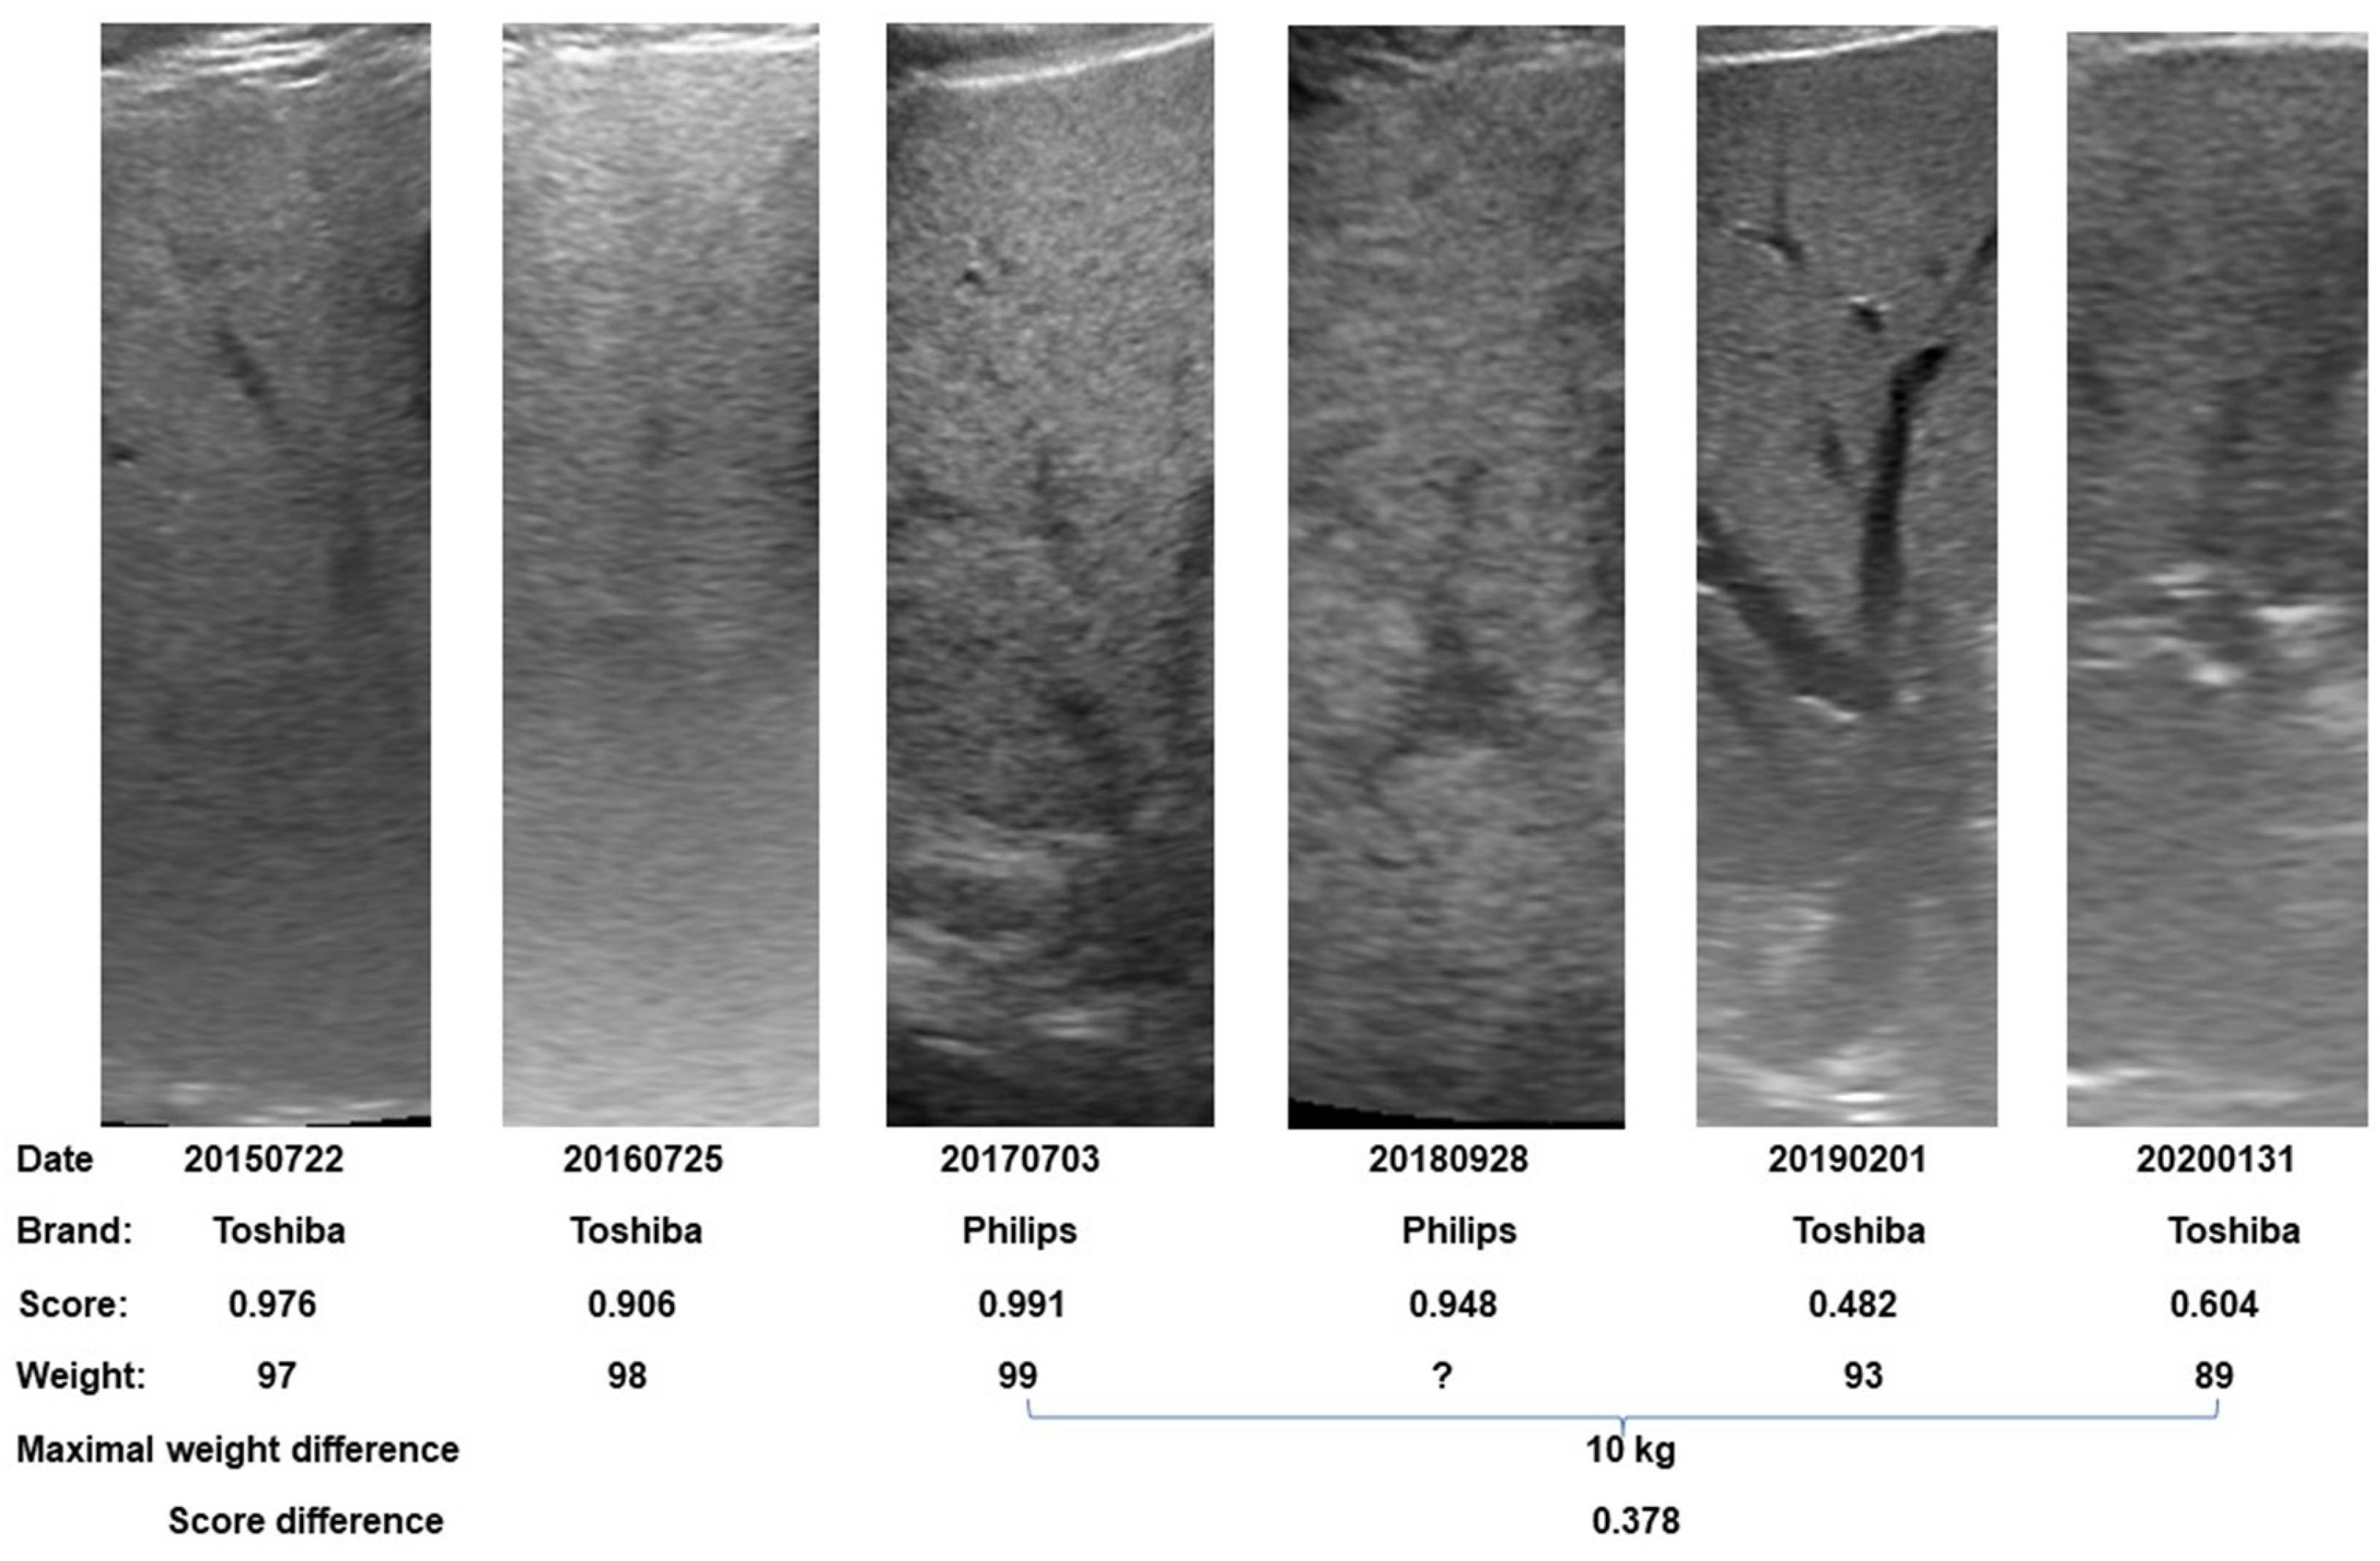

3.3. Correlation between Body Weight and Steatosis Score

3.4. Differences in Steatosis Scores across Gender Differences